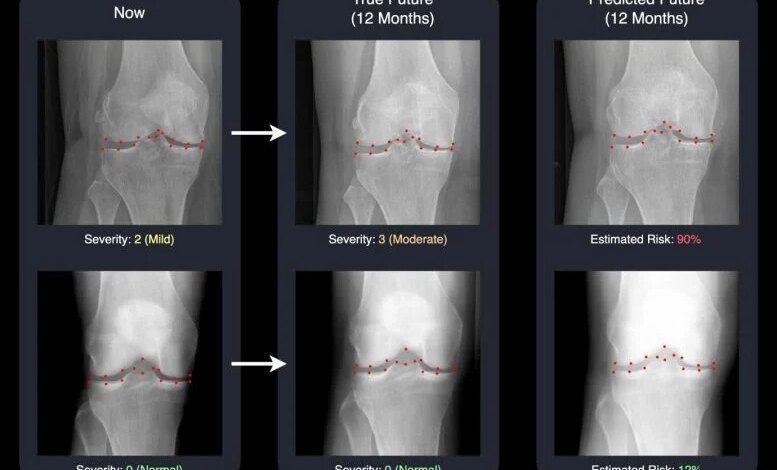

الذكاء الاصطناعي يبعث الحياة في الأشعة السينية القادمة، ويساعد الأطباء على مكافحة التهاب المفاصل عاجلاً

يمكن لنظام الذكاء الاصطناعي الذي تم تطويره في جامعة ساري التنبؤ بالأشعة السينية للركبة في المستقبل، مما يساعد في الكشف عن كيفية تفاقم التهاب المفاصل العظمي بمرور الوقت. ومن خلال تحويل التنبؤات المعقدة إلى صور واضحة، فإنه يمنح الأطباء والمرضى فرصة أفضل للتصرف مبكرًا. ابتكر باحثون في جامعة سري البريطانية نظام ذكاء اصطناعي يمكنه تقدير (…)